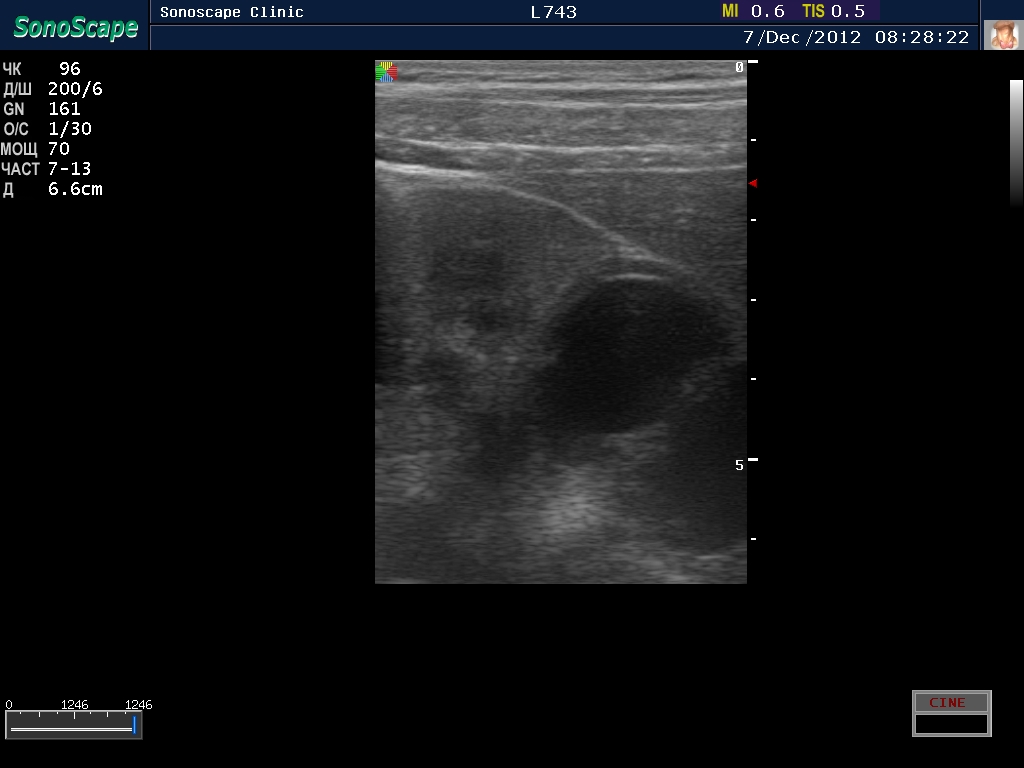

Пациент с подтвержденным туберкулезом почки

Вот как выглядит почка при первом осмотре и в феврале

1.jpg

Видим длительно существующий гидронефроз вследствие процесса в области лоханочно-мочеточникового сегмента (видео 1), с утолщением стенок ЧЛС и истончением паренхимы почки - наиболее частая причина у взрослых - туберкулез.